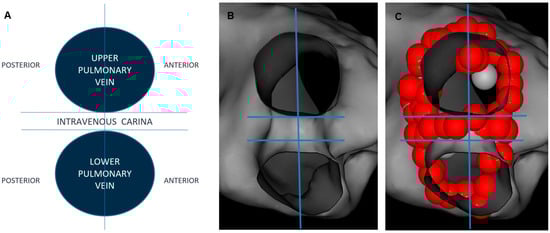

2.3. Ablation Index and Interlesion Distance Guided PVI

2.4. Postprocedural Assessment of Interlesion Distance